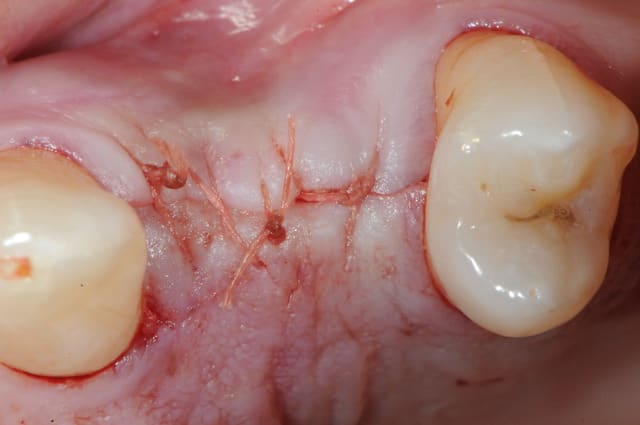

suite..

come ce con de patient fume et picole peut être aussi, il revient à 10 jours avec plusieurs fils de suture de perdu depuis au moins trois jours.

j'explique pourtant longuement aux patients que "si il y a un doute, c'est qu'il n'y a pas de doute"

comprenez, par là que si on pense avoir perdu un fil, j'incite les patients à venir IMMEDIATEMENT et sans RDV.

bref, cet imbé%$µ?"# se pointe et me dit que ça gène un peu.

tu parles! nécrose osseuse, exposition de l'implant et de la crête osseuse photo 1 et 2

donc pince gouge pour l'os "mort" cruantage de berges gingivales, irrigation, sutures bref, je fais le pompier de service.

photo 3: contrôle à 4 jours, le plus grave est passé!

n’empêche que les dégâts sont considérables...la tête de l'implant est exposée.